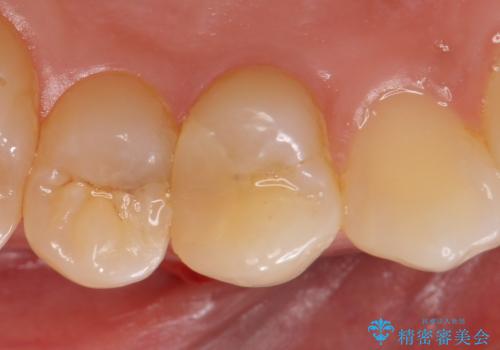

右上4は根管治療を行い、オールセラミッククラウンによる補綴を行いました。

今回用いたオールセラミッククラウンはジルコニアフレームという白い素材の上にセラミックを盛っているため、審美性が非常に高いのが特徴です。

また、ジルコニアは人工ダイヤモンドの材料にも使われているほど高い強度を持っており、そのためオールセラミッククラウンは審美性だけでなく、奥歯やブリッジの補綴も可能とするクラウンです。